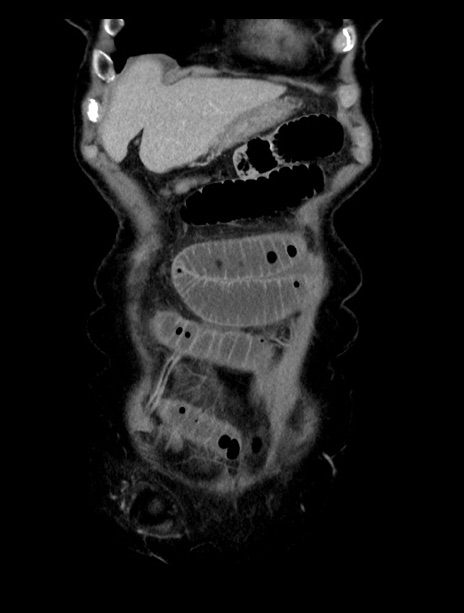

症例23(冠状断像)

【症例】70歳代女性

【主訴】下腹部痛・嘔吐

【現病歴】2日前より腹痛あり。昨日嘔吐あり。症状改善しないため来院。

【既往歴】胃GISTに対して胃部分切除後。

【身体所見】BT 37.1℃、BP 128/77mmHg、腹部:平坦・軟、下腹部に圧痛あり。

【データ】WBC 10200、CRP 0.31